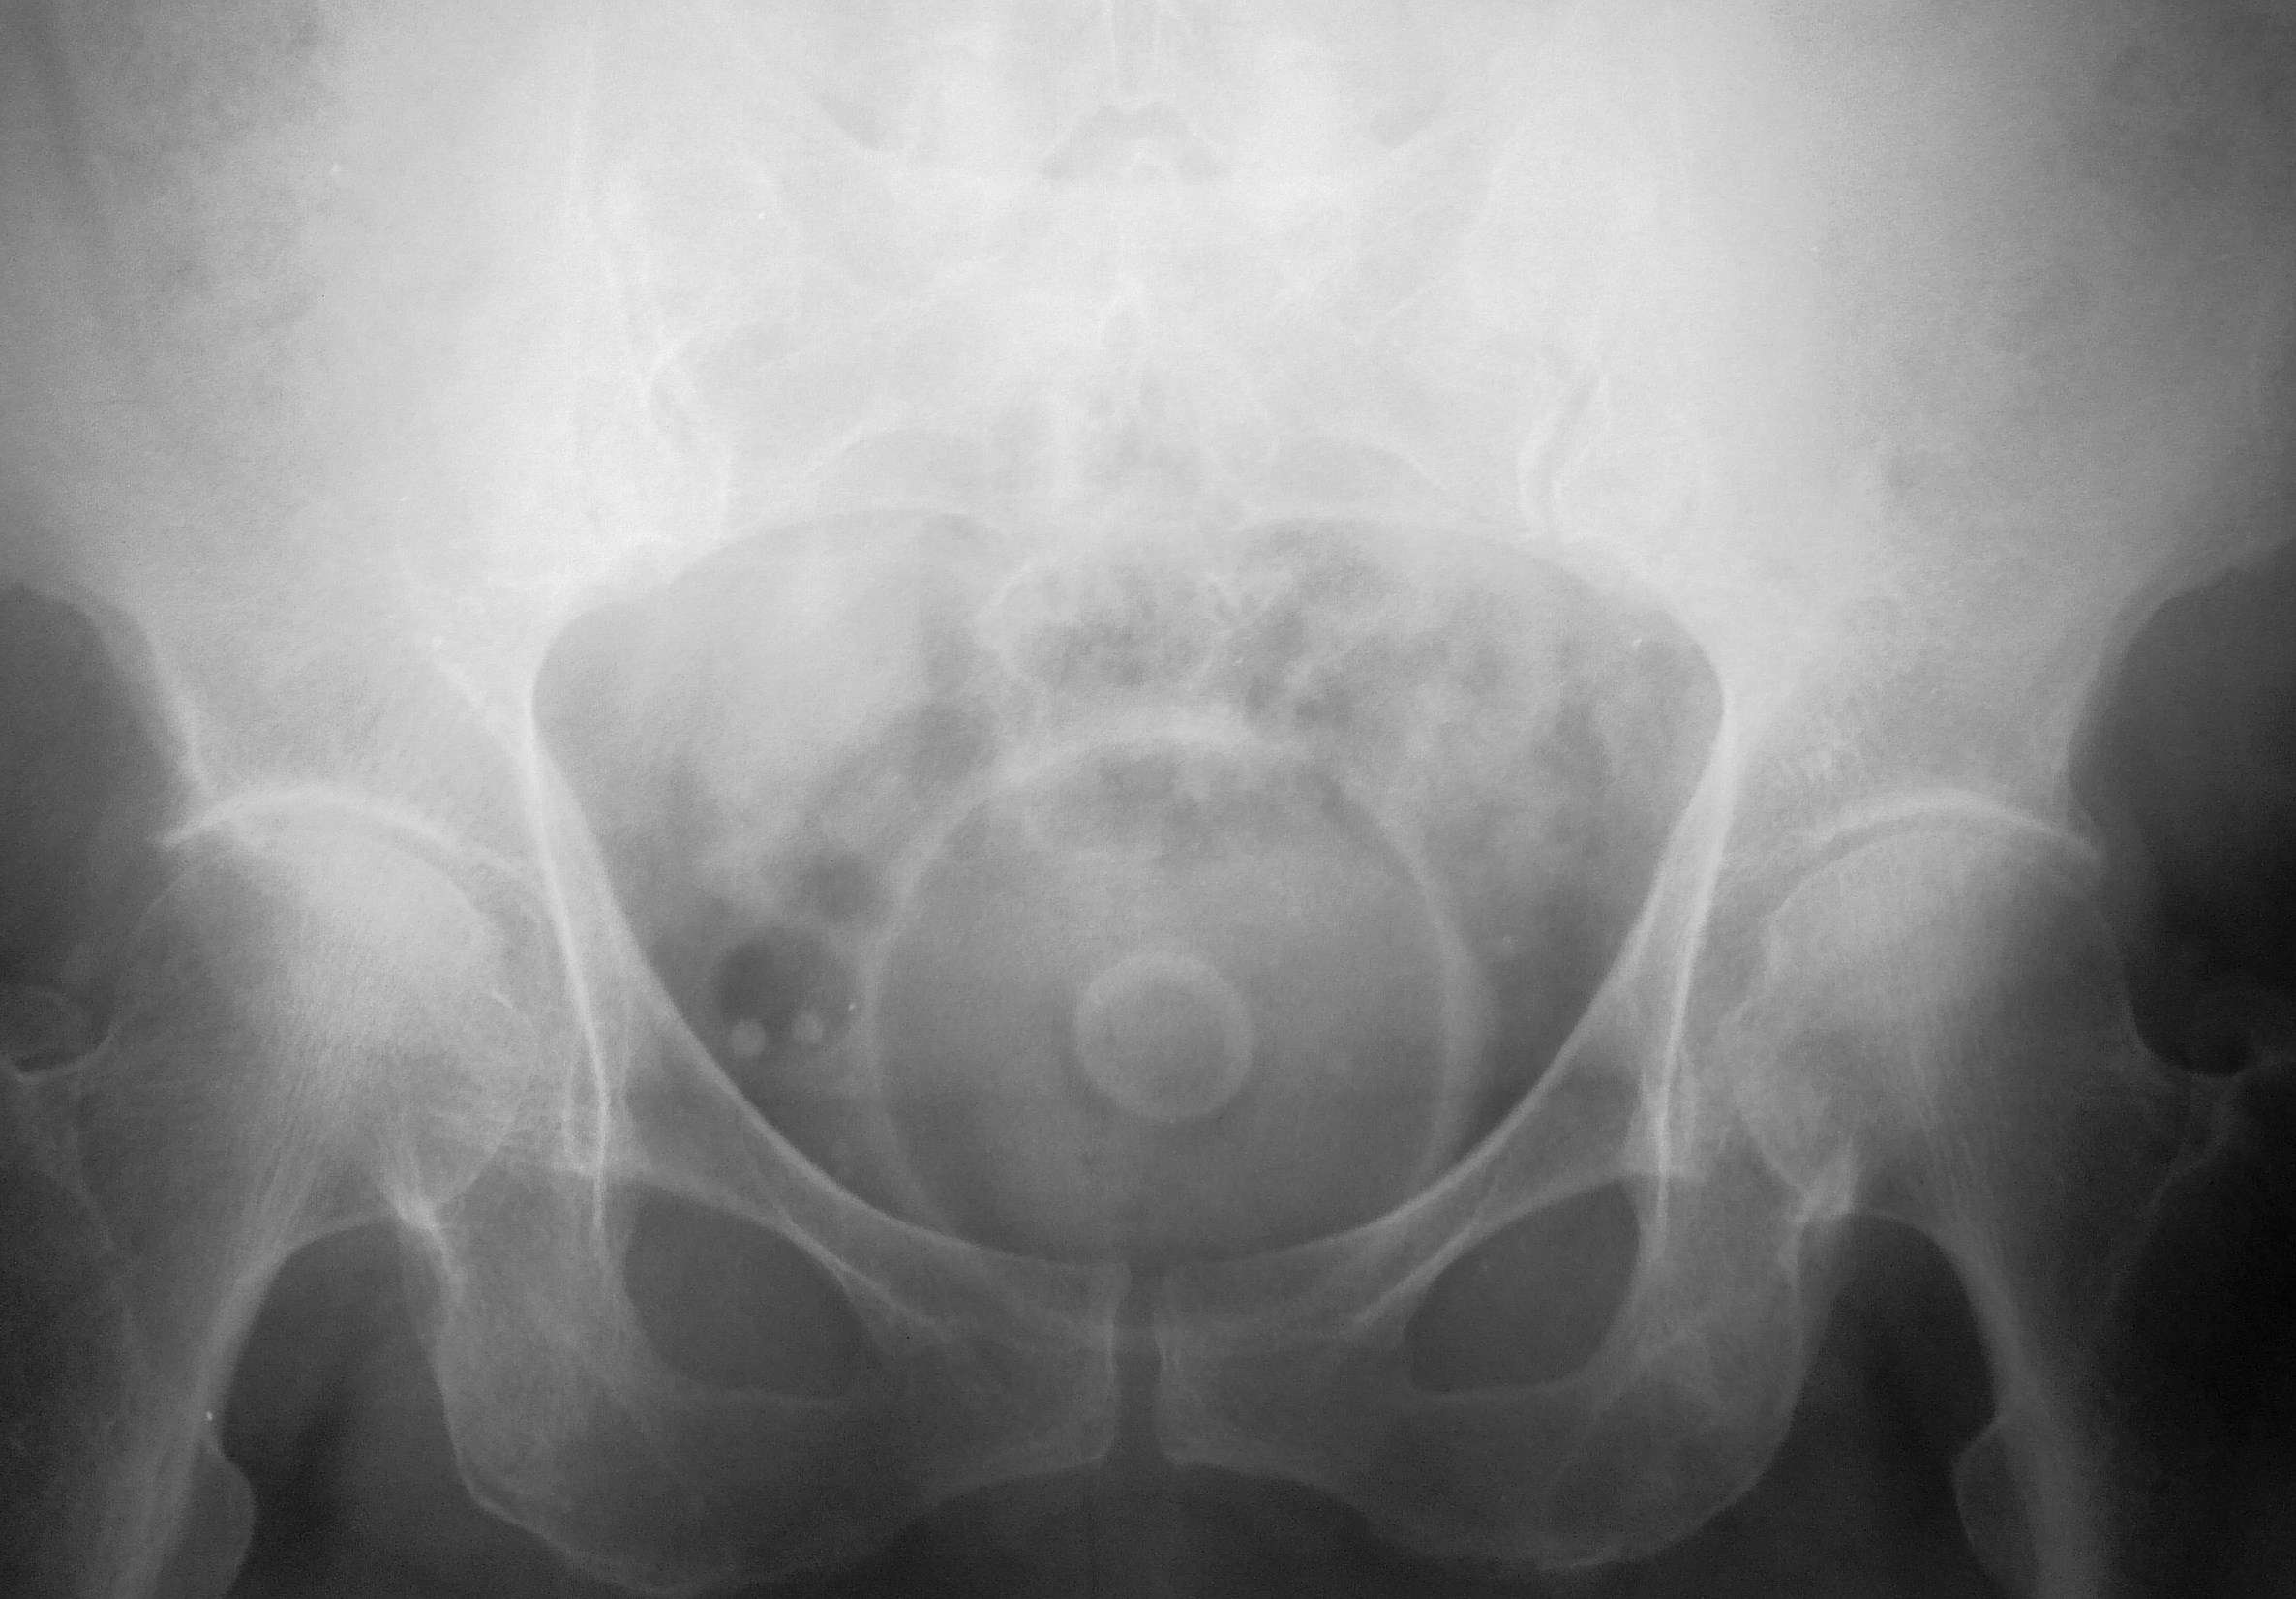

Тоже попадается нередко. Маточное кольцо, применяется при опущении матки.

Бабушку распрашивал с пристрастием, что да как, были ли какие то операции, кое как вспомнила что когдА-то, что -то было по гинекологии, я тоже вижу впервые, но понял сразу, что ЭТО не "организменногенное"

Может быть кому и нередко, а я то вижу в первый раз. Думал, медуза какая-то.

Ежли по чесноку я сначало подумал, что это диафрагма, помниться был такое противозачаточное изделие